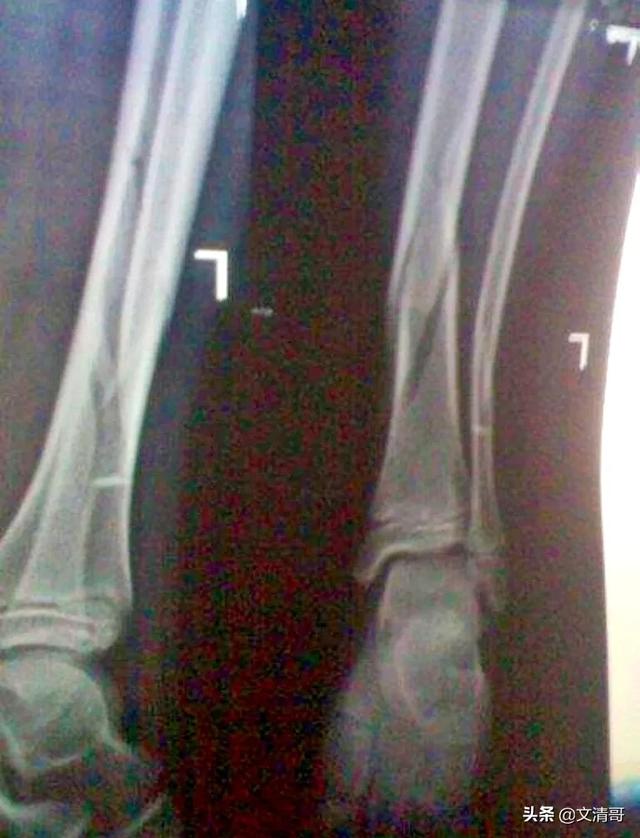

- embolie graisseuse L'embolie graisseuse est une complication grave de la chirurgie post-traumatique ou orthopédique.La cause la plus fréquente de cette maladie est une alimentation riche en graisses.Fractures des os longs, telles que les fractures du fémur. Ce phénomène est dû à la libération des adipocytes de la graisse des os ou des tissus mous après la rupture d'une blessure localisée et à l'invasion de gouttelettes de graisse dans le flux sanguin veineux, où se produit une embolie graisseuse d'organes et de tissus, principalement dans la vascularisation pulmonaire et cérébrale. Elle survient 3 à 72 heures après un traumatisme ou une fracture et peut se produire pendant la période périopératoire.

Un autre type d'accident qui tend à se produire en orthopédie s'appelle unembolie graisseuse.. En d'autres termes, les cellules adipeuses se rompent pour libérer des gouttelettes de lipides, et ces gouttelettes de lipides se retrouvent dans les cellules adipeuses.goutte grasseUne petite quantité de gouttelettes lipidiques dans le sang n'entraîne pas trop de problèmes, mais s'il y a un grand nombre de gouttelettes lipidiques, par exemple de 9 à 20 grammes, une fois dans la circulation sanguine, il est possible de provoquer une embolie graisseuse, mais il est possible de provoquer une embolie graisseuse dans la circulation sanguine.circulation pulmonaireIl peut en résulter une obstruction d'environ 75 % de la zone de circulation pulmonaire, et le patient peut souffrir d'asphyxie et d'insuffisance cardiaque aiguë entraînant la mort.

Cette embolie graisseuse se forme parfois au moment de la fracture, et parfois elle est provoquée par un tel accident lors d'une intervention chirurgicale.

Il était une fois un jeunefracture comminutive de la tige fémoraleAprès l'hospitalisation et les préparatifs préopératoires, la veille de l'intervention chirurgicale envisagée, le patient a eu un changement d'humeur soudain, avec une irritabilité marquée, qui a conduit à un babillage et à un délire, et finalement à une perte de conscience, ce qui est un cas typique deembolie graisseuseDéclenché par les symptômes, ce patient n'a finalement pas été réanimé ......